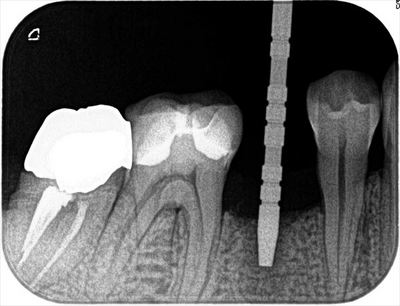

局所麻酔後に安全な深度までドリリングして深度ゲージを挿入しレントゲンを撮影します。

予定通りでしたのでこのままドリルステップを進めます。

オペ終了時のレントゲン写真です。